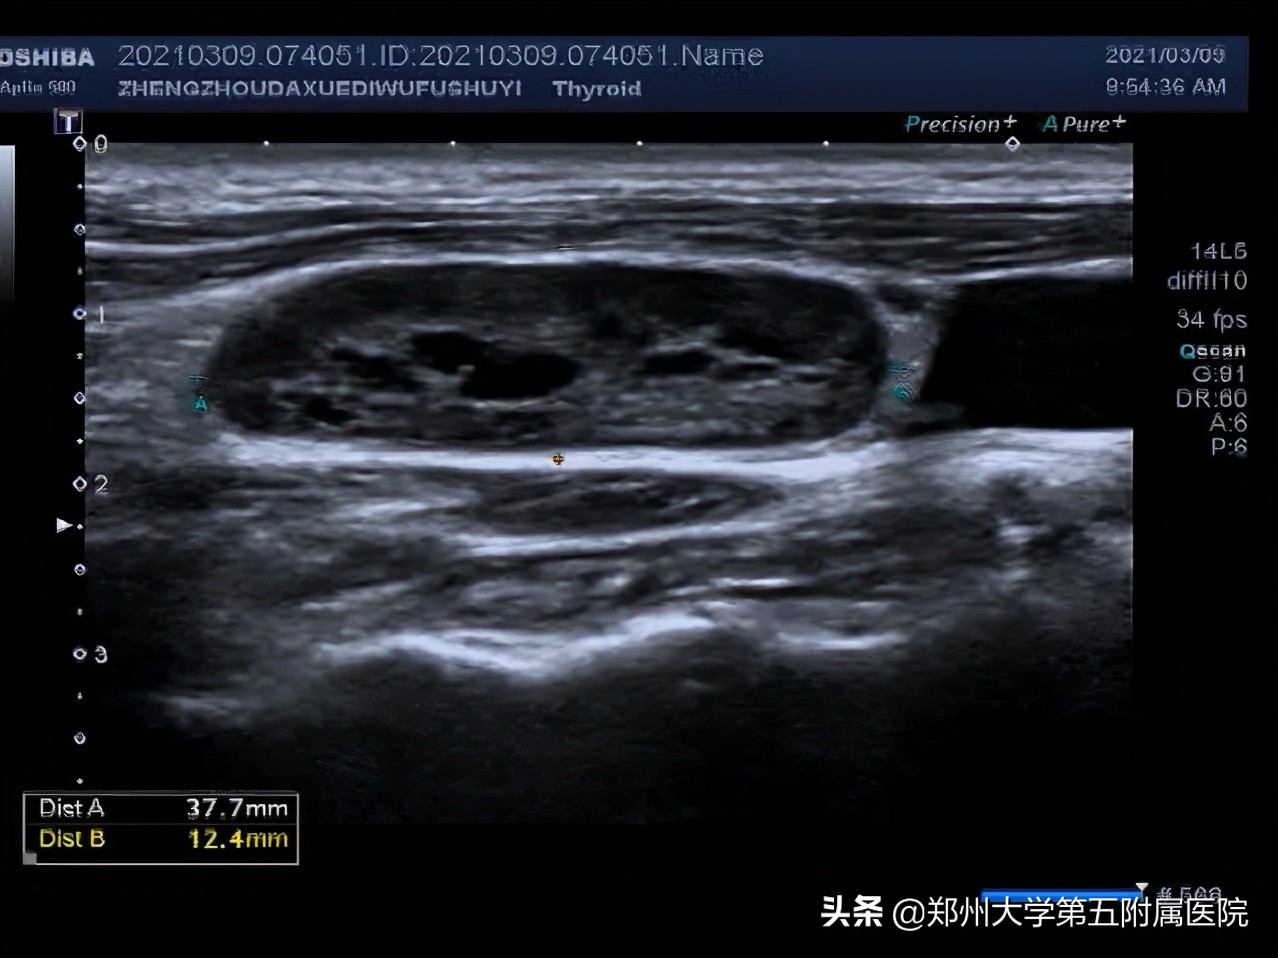

从彩超上看这个淋巴结的很多征象都提示它是恶性的,鼻咽癌比较隐匿,多例鼻咽癌就是这样发现的。

1.淋巴结皮髓质分界不清

2.淋巴结内部有液化

3.淋巴结血流为周边型,没有淋巴门。

2.不疼不痒、进行性肿大淋巴结:这些淋巴结要注意了!需要到医院做彩超检查,检查前不需要特殊准备。超声看到淋巴结内有液化、钙化、淋巴结变圆,皮髓质分界不清,淋巴结相互融合、淋巴结血流为周边型、淋巴门消失等就可能是淋巴瘤、结核、转移性肿瘤、结节病等,需告知临床医生进行进一步检查明确诊断。